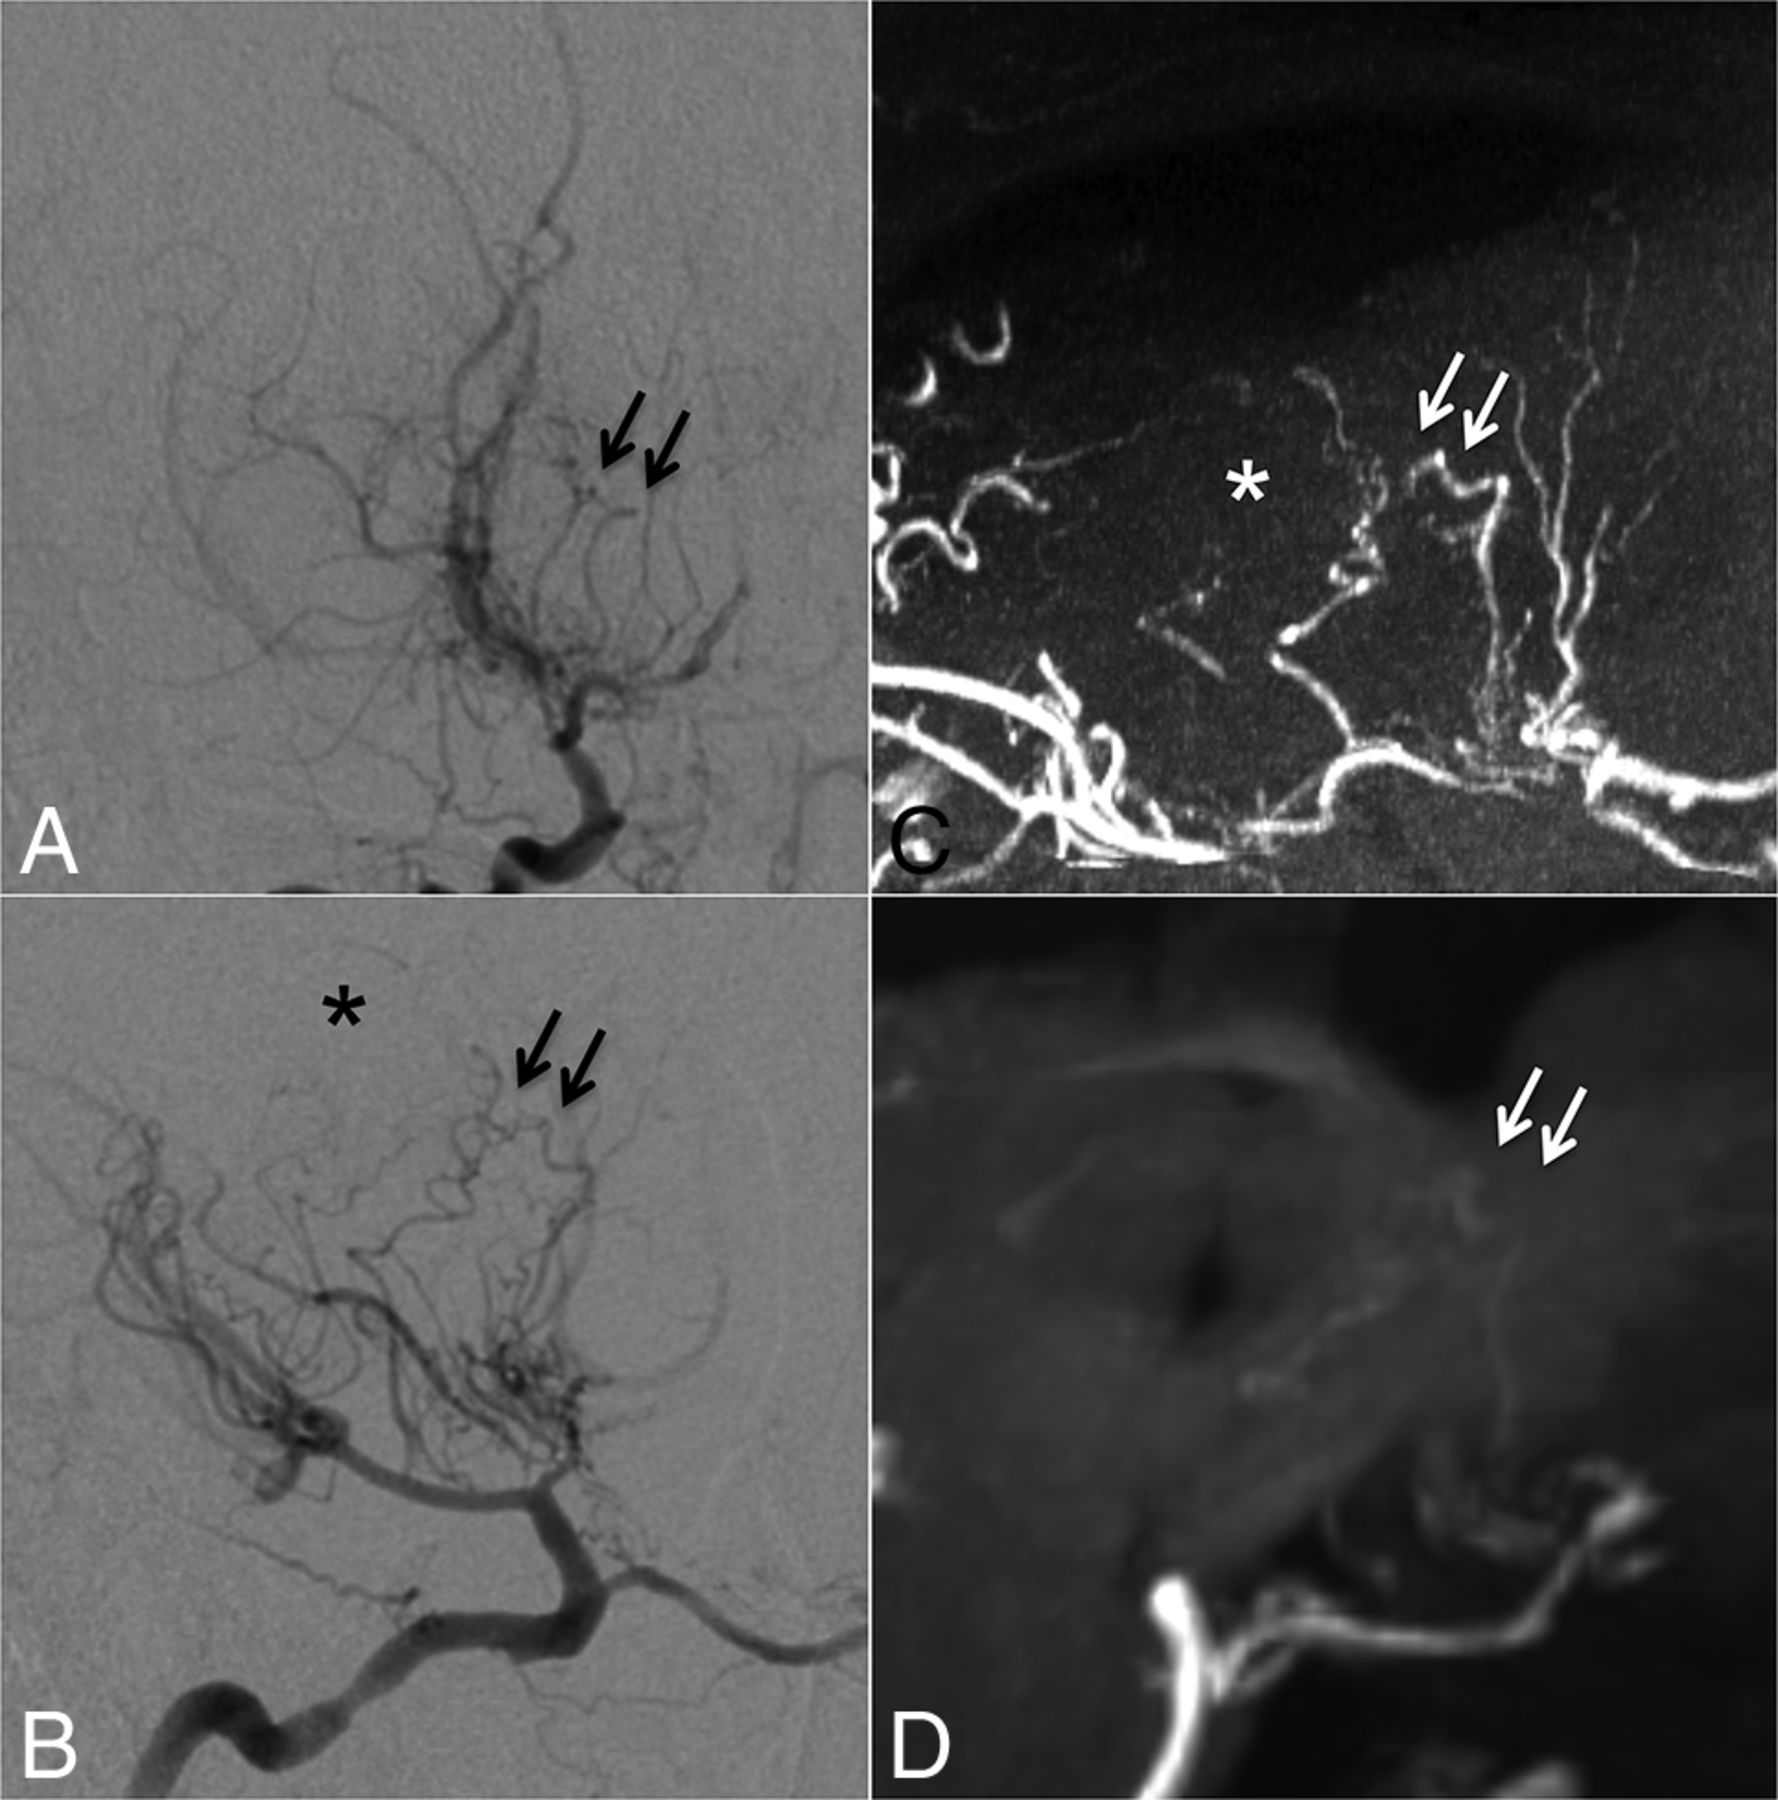

DSCNs had pathways connecting to 2 cortical vessels: either the peripheral MCA or the anterior cerebral artery. Most anastomoses were detected between either choroidal arteries or striate arteries and cortical arteries directly or via medullary arteries (type a: Fig 2). Septal transcallosal anastomoses between choroidal arteries and pericallosal arteries were also identified (type b: Fig 2).

Case 1. Selective right internal carotid angiography (anteroposterior, A; lateral view, B) shows anastomotic connections to cortical arteries from the anterior choroidal artery (black arrowheads, type b) as well as from thalamostriate arteries (white arrows, type a). Collateral networks are excellently visualized in MIP from TOF-MRA with slab thickness of 20 mm (white arrows and black arrowheads) (C). Transcallosal connections to cortical arteries (white arrowheads) not detected by DSA are poorly visualized on MPRAGE (D).